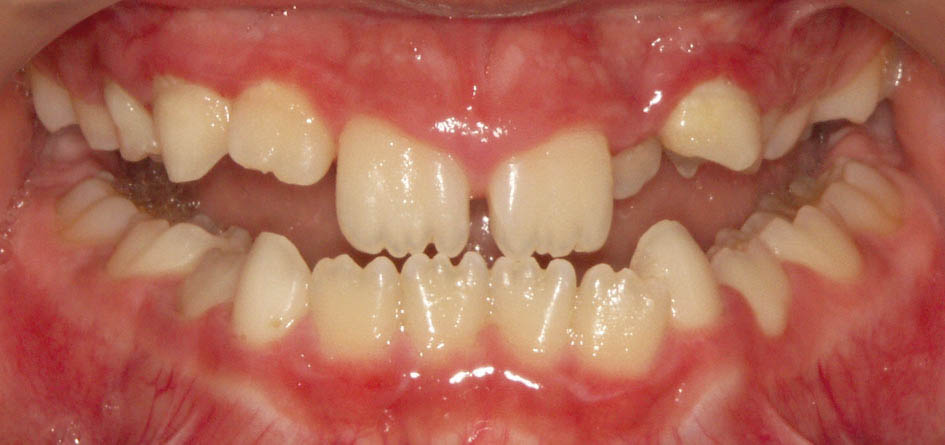

اگر دیستال E بالا و پایین در یک راستا باشند احتمالاً کلاسI میشود (شکل 21-5). شاید عدهای از همین گروه در آینده کلاسII نیز بشوند.

شکل 21-5: دیستال دندانهای E بالا و پائین در یک راستا هستند